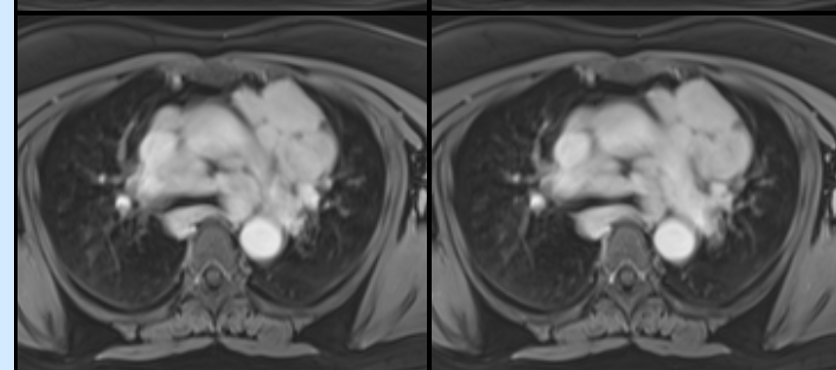

Granulomatous Cardiomyopathy

Pulmonary sarcoidosis